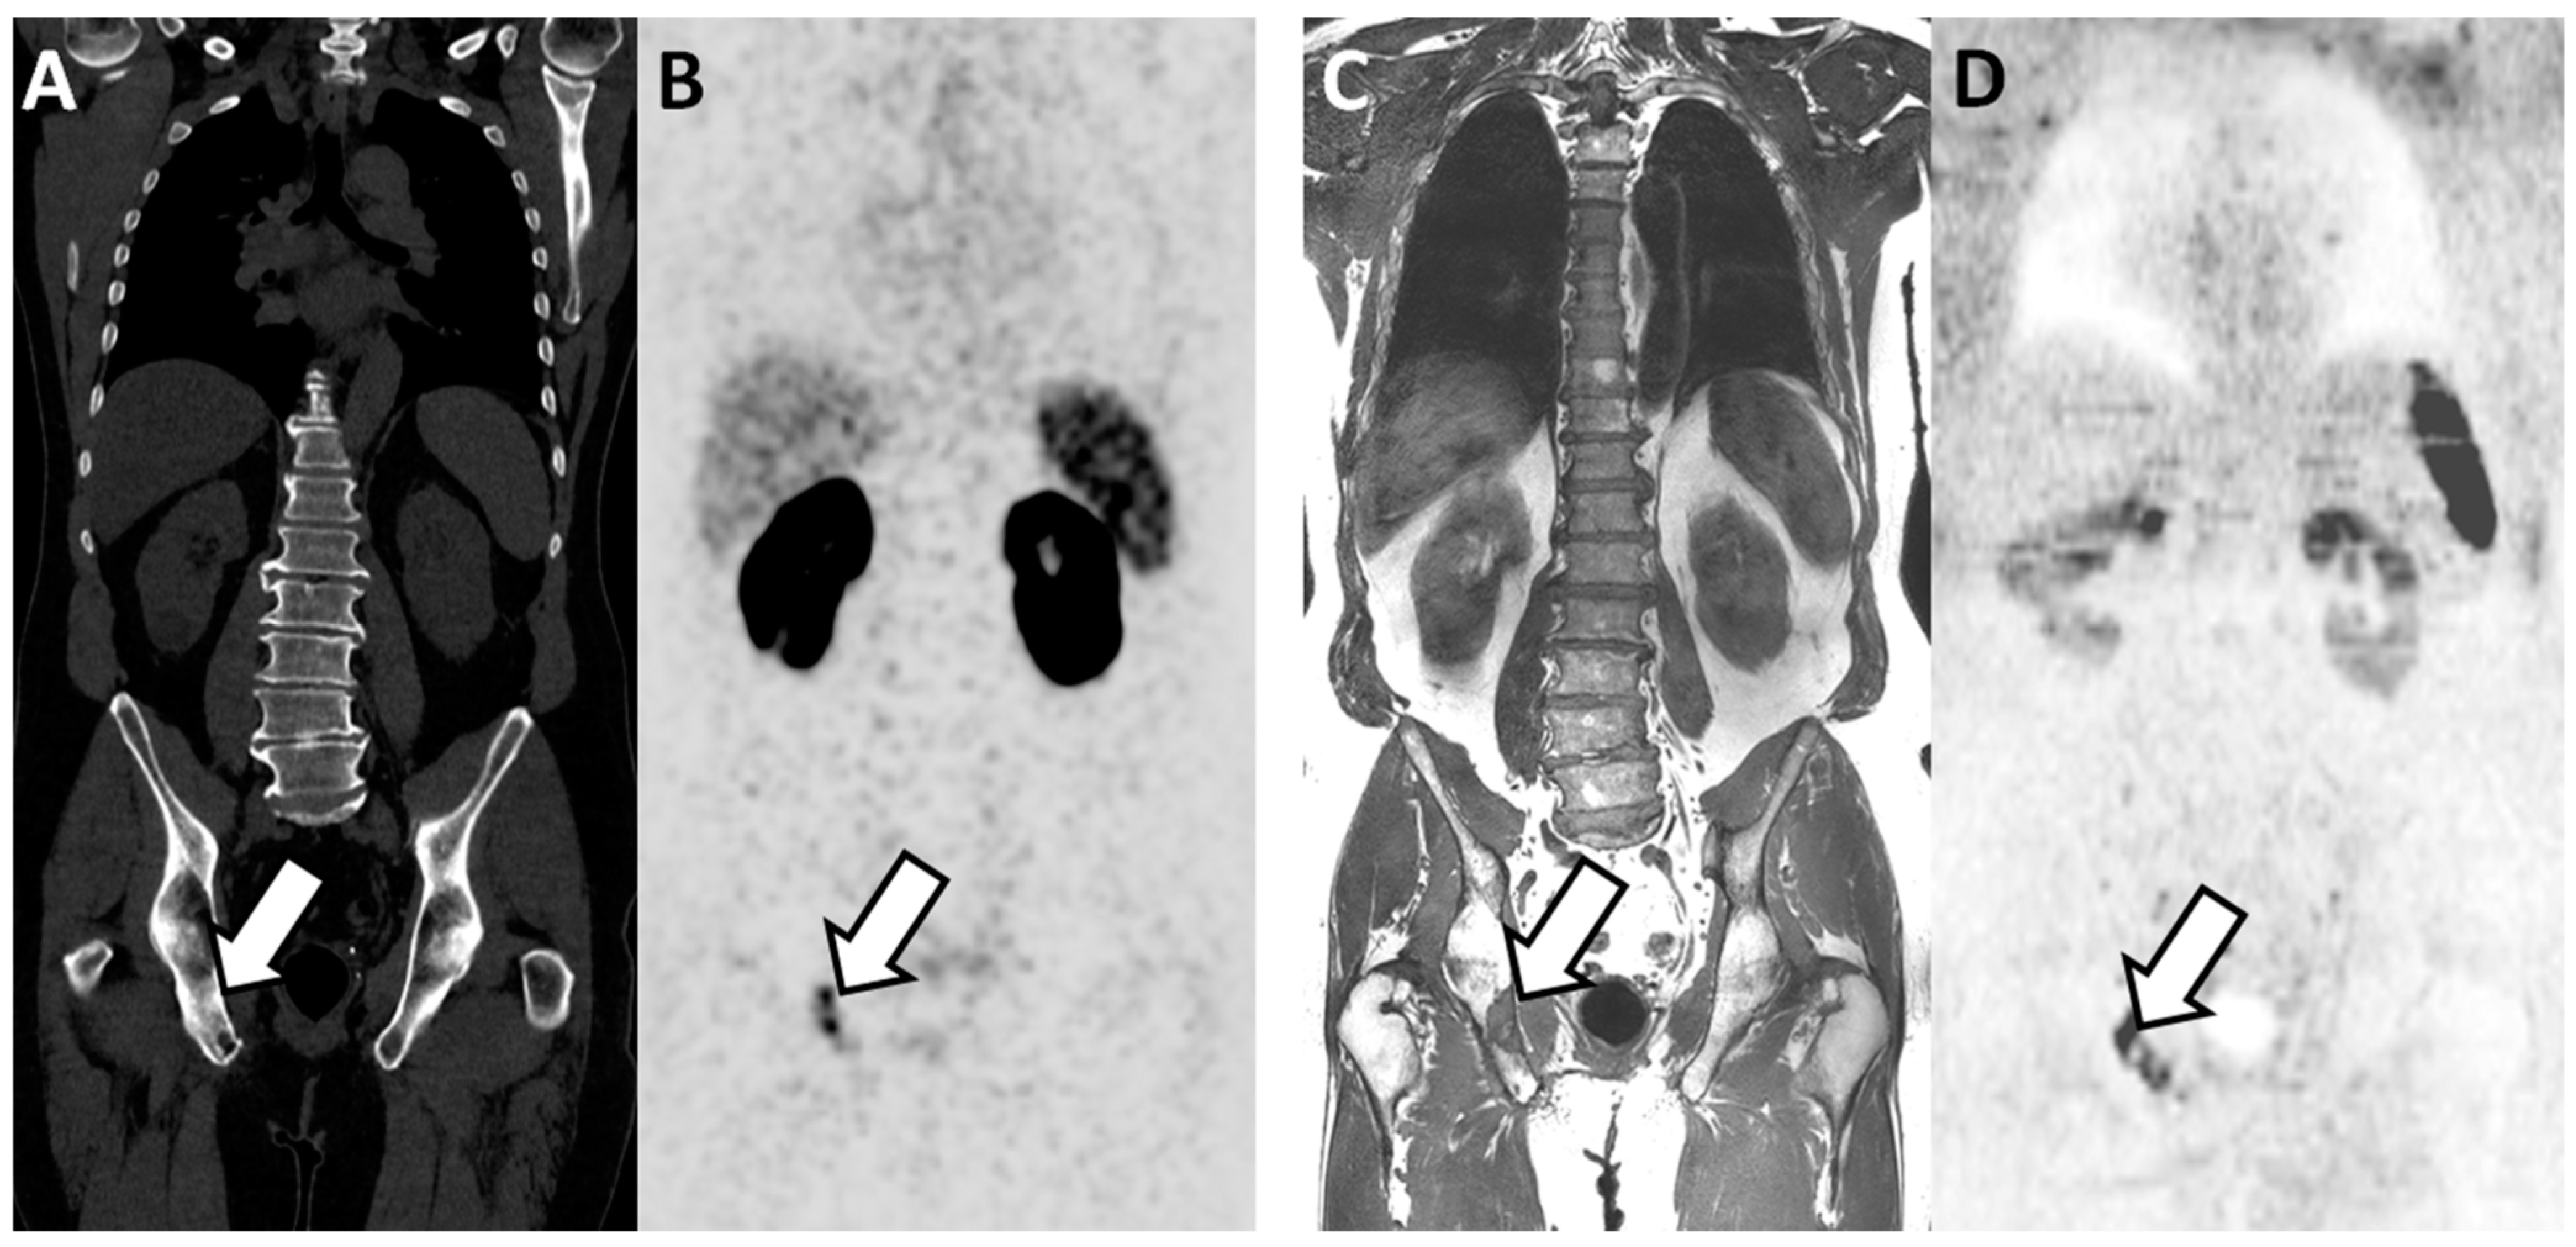

Figure 2. Concordant findings between PSMA PET/CT and WB-MRI/DWI: true positive observation of bone metastasis by WB-MRI/DWI in 65-year-old patient with ND prostate cancer at high risk for metastasis. (A,B) PSMA PET/CT: reformatted coronal CT (A) and PET (B) images show sclerotic lesion within the right ilio-ischiatic ramus with evident tracer uptake (arrows in (A,B)). (C,D) WB-MRI/DWI images: corresponding reformatted high resolution T1 (C) and diffusion-weighted (D) MRI images show bone lesion of low signal intensity on T1 and high signal intensity on MR images (inverted grey scale in the figure) within the right ilio-ischiatic ramus. The best valuable comparator confirmed the metastatic nature of the lesion.

PSMA PET-CT significantly outperformed WB-MRI (Table 4). At the patient level, the AUC was 0.96 (0.92–1.00) and 0.87 (0.79–0.95) for PSMA PET-CT and for WB-MRI, respectively (p = 0.045). The inter-technique agreement was good (adjusted kappa = 0.70; 0.55–0.86). The AUC for pathological lymph node detection was 0.98 (0.96–1.00) and 0.83 (0.74–0.92) for PSMA PET-CT and WB-MRI, respectively (p = 0.002). The AUC for bone metastases detection was 0.94 (0.87–1.00) and 0.99 (0.96–1.00) for PSMA-PET and WB-MRI, respectively (p = 0.24) (Figure 2). At the bone level, WB-MRI detected all lesions, whereas PSMA PET-CT missed one.